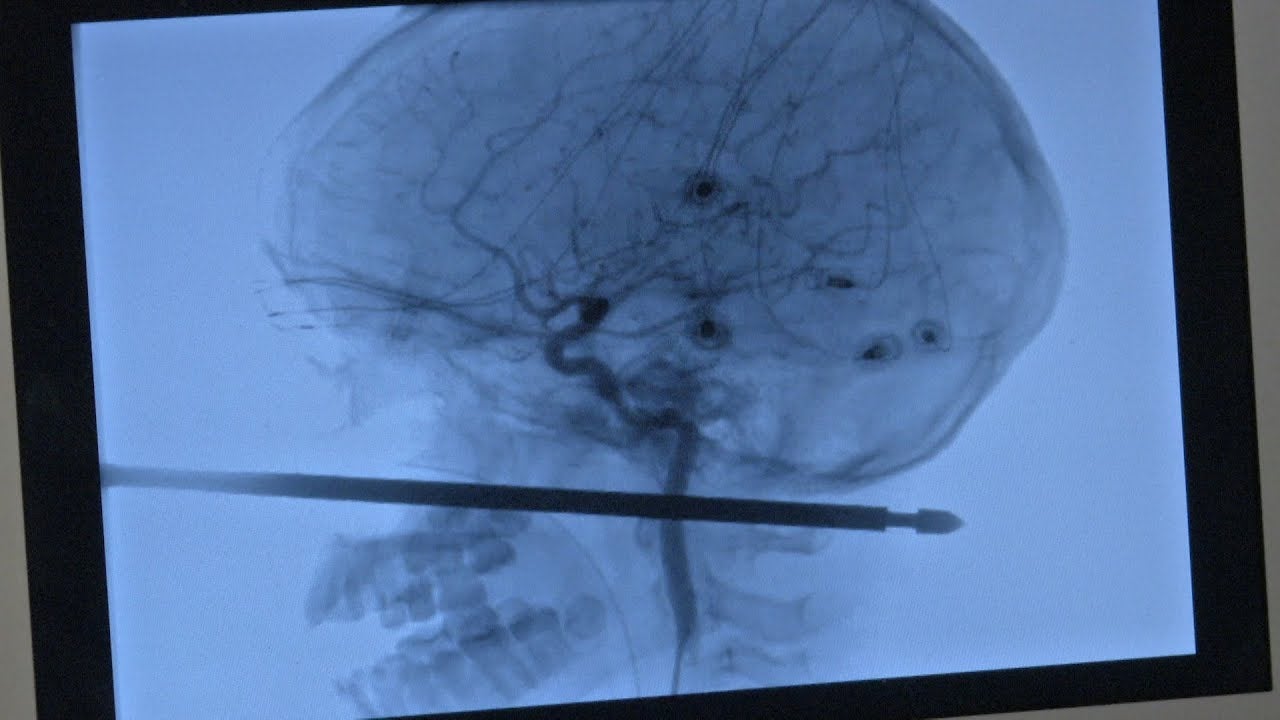

Cuando Xavier Cunningham saltó de la casa huyendo de las avispas, cayó de bruces sobre un pincho de barbacoa que sobresalía de la hierba. Según comentó su padre, Cunningham y sus amigos habían encontrado la barra de metal en el patio antes, y la colocaron en el suelo para que nadie la pisara. El pincho entró por la mejilla de Cunningham, le perforó el cráneo y le atravesó la cabeza.

“Escuché gritos y bajé corriendo las escaleras”, le dijo la madre de Cunningham, Gabrielle Miller, al Kansas City Star. “Entro dentro y tenía ese palo atravesado completamente.” El otro extremo del pincho sobresalía aproximadamente 15 centímetros de la cara de Cunningham.

“Aquella cosa había pasado sin tocar sus ojos, ni su cerebro ni su médula espinal”, dijo Koji Ebersole, director de neurocirugía endovascular en el Sistema de Salud de la Universidad de Kansas. “Pero la principal preocupación que teníamos eran los vasos sanguíneos en el cuello”.

Los escaneos mostraron que el palo había pasado sin tocar ninguno de los vasos principales. “No podrías haber salido mejor”, dijo Ebersole. “Poder pasar 13 o 14 centímetros desde la parte frontal de la cara hacia atrás y no haber golpeado ninguna de estas cosas es algo que ocurre una vez entre un millón”. Aquí hay un vídeo de Ebersole discutiendo la operación: